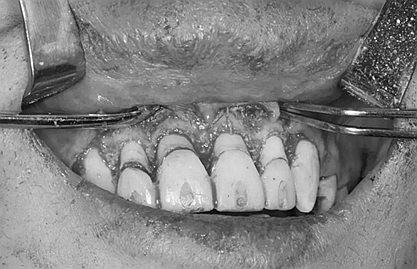

第二次治療是半個月后,這次做了根管充填后將覆蓋在我們身體上的一部分牙齦切除,讓我們埋于牙齦下的身體暴露了一部分,也就是醫(yī)生說的冠延長術(shù)。這是為了讓我們變得美觀一些。

冠延長術(shù)